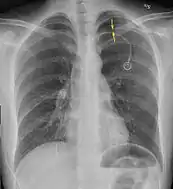

Anteroposterior expired X-ray at the same time, more clearly showing the pneumothorax in this case

It is not unusual for the mediastinum (the structure between the lungs that contains the heart, great blood vessels, and large airways) to be shifted away from the affected lung due to the pressure differences. This is not equivalent to a tension pneumothorax, which is determined mainly by the constellation of symptoms, hypoxia, and shock.[13]

The size of the pneumothorax (i.e. the volume of air in the pleural space) can be determined with a reasonable degree of accuracy by measuring the distance between the chest wall and the lung. This is relevant to treatment, as smaller pneumothoraces may be managed differently. An air rim of 2 cm means that the pneumothorax occupies about 50% of the hemithorax.[15] British professional guidelines have traditionally stated that the measurement should be performed at the level of the hilum (where blood vessels and airways enter the lung) with 2 cm as the cutoff,[15] while American guidelines state that the measurement should be done at the apex (top) of the lung with 3 cm differentiating between a "small" and a "large" pneumothorax.[33] The latter method may overestimate the size of a pneumothorax if it is located mainly at the apex, which is a common occurrence.[15] The various methods correlate poorly but are the best easily available ways of estimating pneumothorax size.[15][19] CT scanning (see below) can provide a more accurate determination of the size of the pneumothorax, but its routine use in this setting is not recommended.[33]

Not all pneumothoraces are uniform; some only form a pocket of air in a particular place in the chest.[15] Small amounts of fluid may be noted on the chest X-ray (hydropneumothorax); this may be blood (hemopneumothorax).[13] In some cases, the only significant abnormality may be the "deep sulcus sign", in which the normally small space between the chest wall and the diaphragm appears enlarged due to the abnormal presence of fluid.[16]